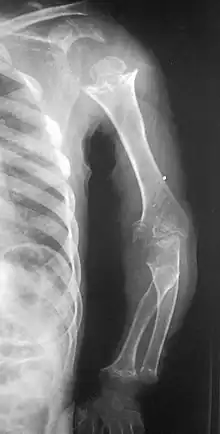

Pseudoachondroplasia. Shoulders and Humeri. Note the dysplastic proximal humeral epiphyses, metaphyseal broadening, irregularity and metaphyseal line of ossification. These changes are collectively known as "rachitic-like changes". Lesions are bilateral and symmetrical. | |

- Dysplastic/hypoplastic epiphyses especially of shoulders and around the knees.

- Metaphyseal broadening, irregularity and metaphyseal line of ossification. These abnormalities that are typically encountered in proximal humerus and around the knees are collectively known as “rachitic-like changes”.

- Radiographic lesions of the appendicular skeleton are typically bilateral and symmetric.